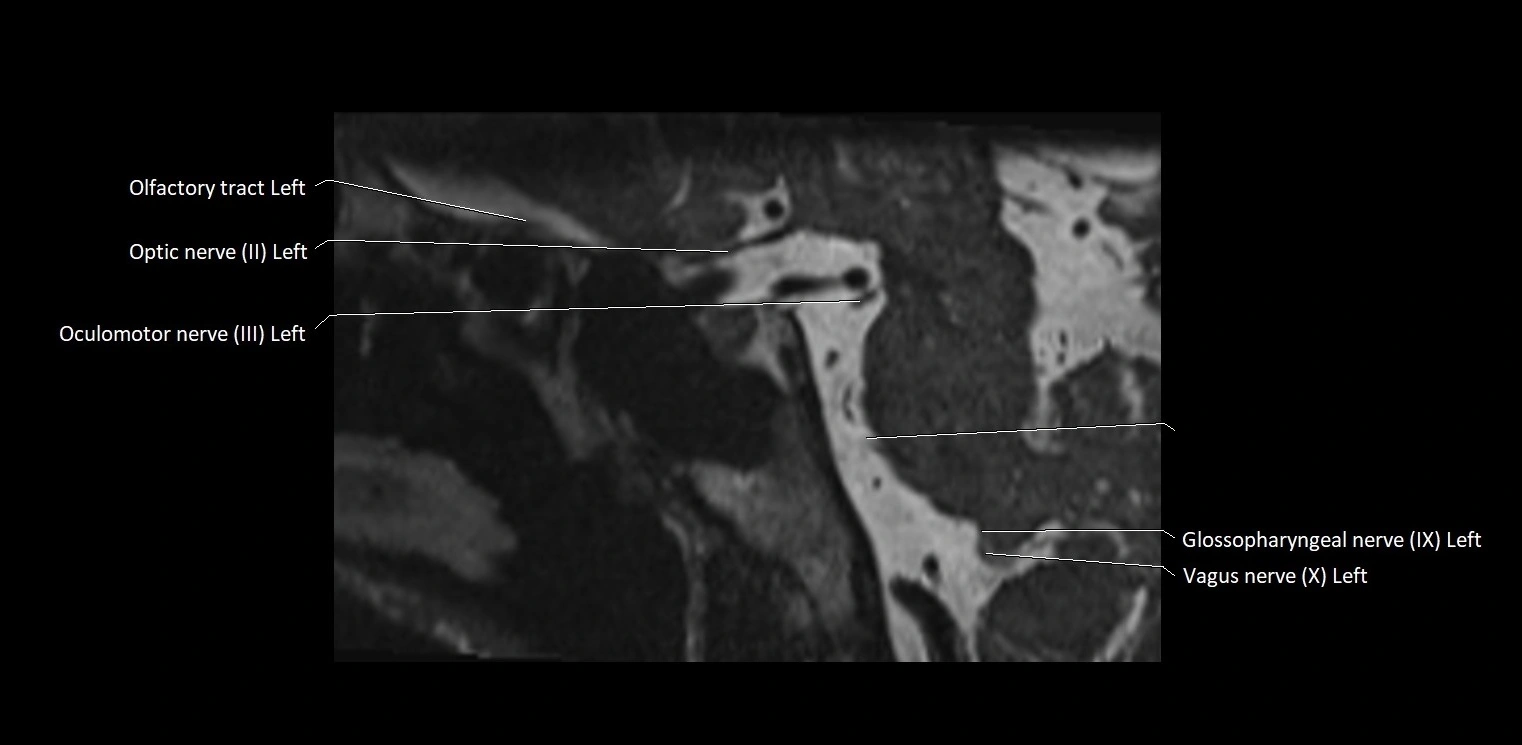

MRI Appearance

• The abducens nerve is a small, thin, linear structure

• Best visualized on high-resolution T2-weighted 3D MRI sequences (e.g., FIESTA or CISS)

• Seen as a hypointense (dark) line running from the brainstem at the pontomedullary junction, traversing the prepontine cistern, and entering Dorello’s canal under the petrosphenoidal ligament, then into the cavernous sinus, and finally the orbit

• May be challenging to visualize in standard MRI due to its small size

• Pathology may be inferred by absence, displacement, or enhancement of the nerve